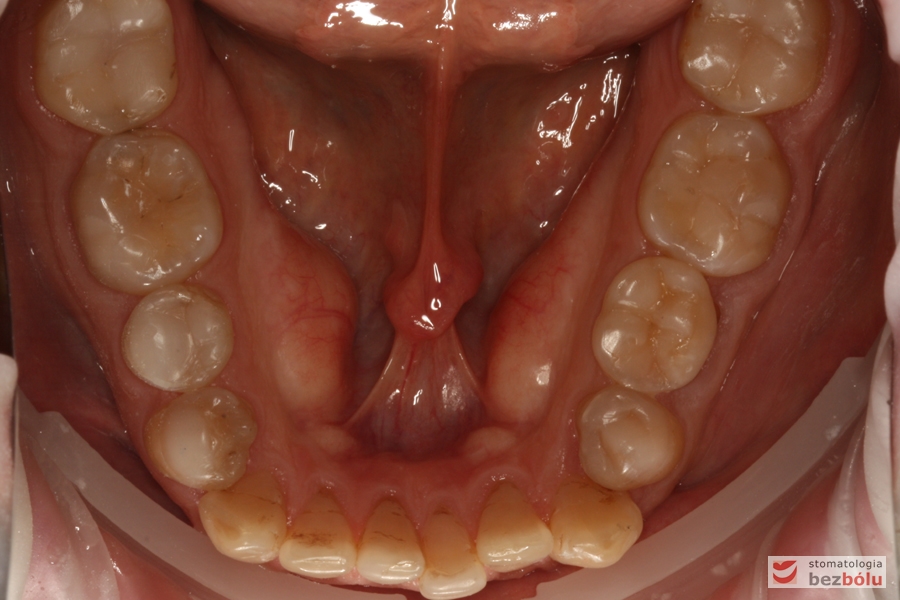

Szczęka - widok okluzyjny, liczne starcia i ubytki szkliwa, nieregularna obwiednia łuku

Szczęka – widok okluzyjny, liczne starcia i ubytki szkliwa, nieregularna obwiednia łuku